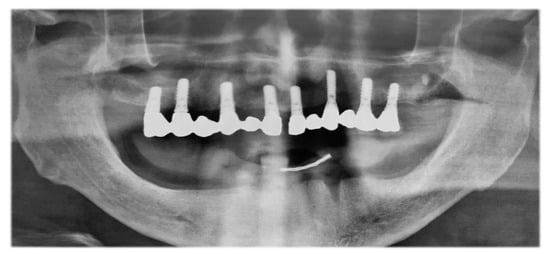

The patient presented a fixed maxillary prosthesis on 8 ITI dental implants that were inserted 15 years ago, and had total edentulous in the mandible (Figure 3).

Figure 3.

Preoperative panoramic radiograph.